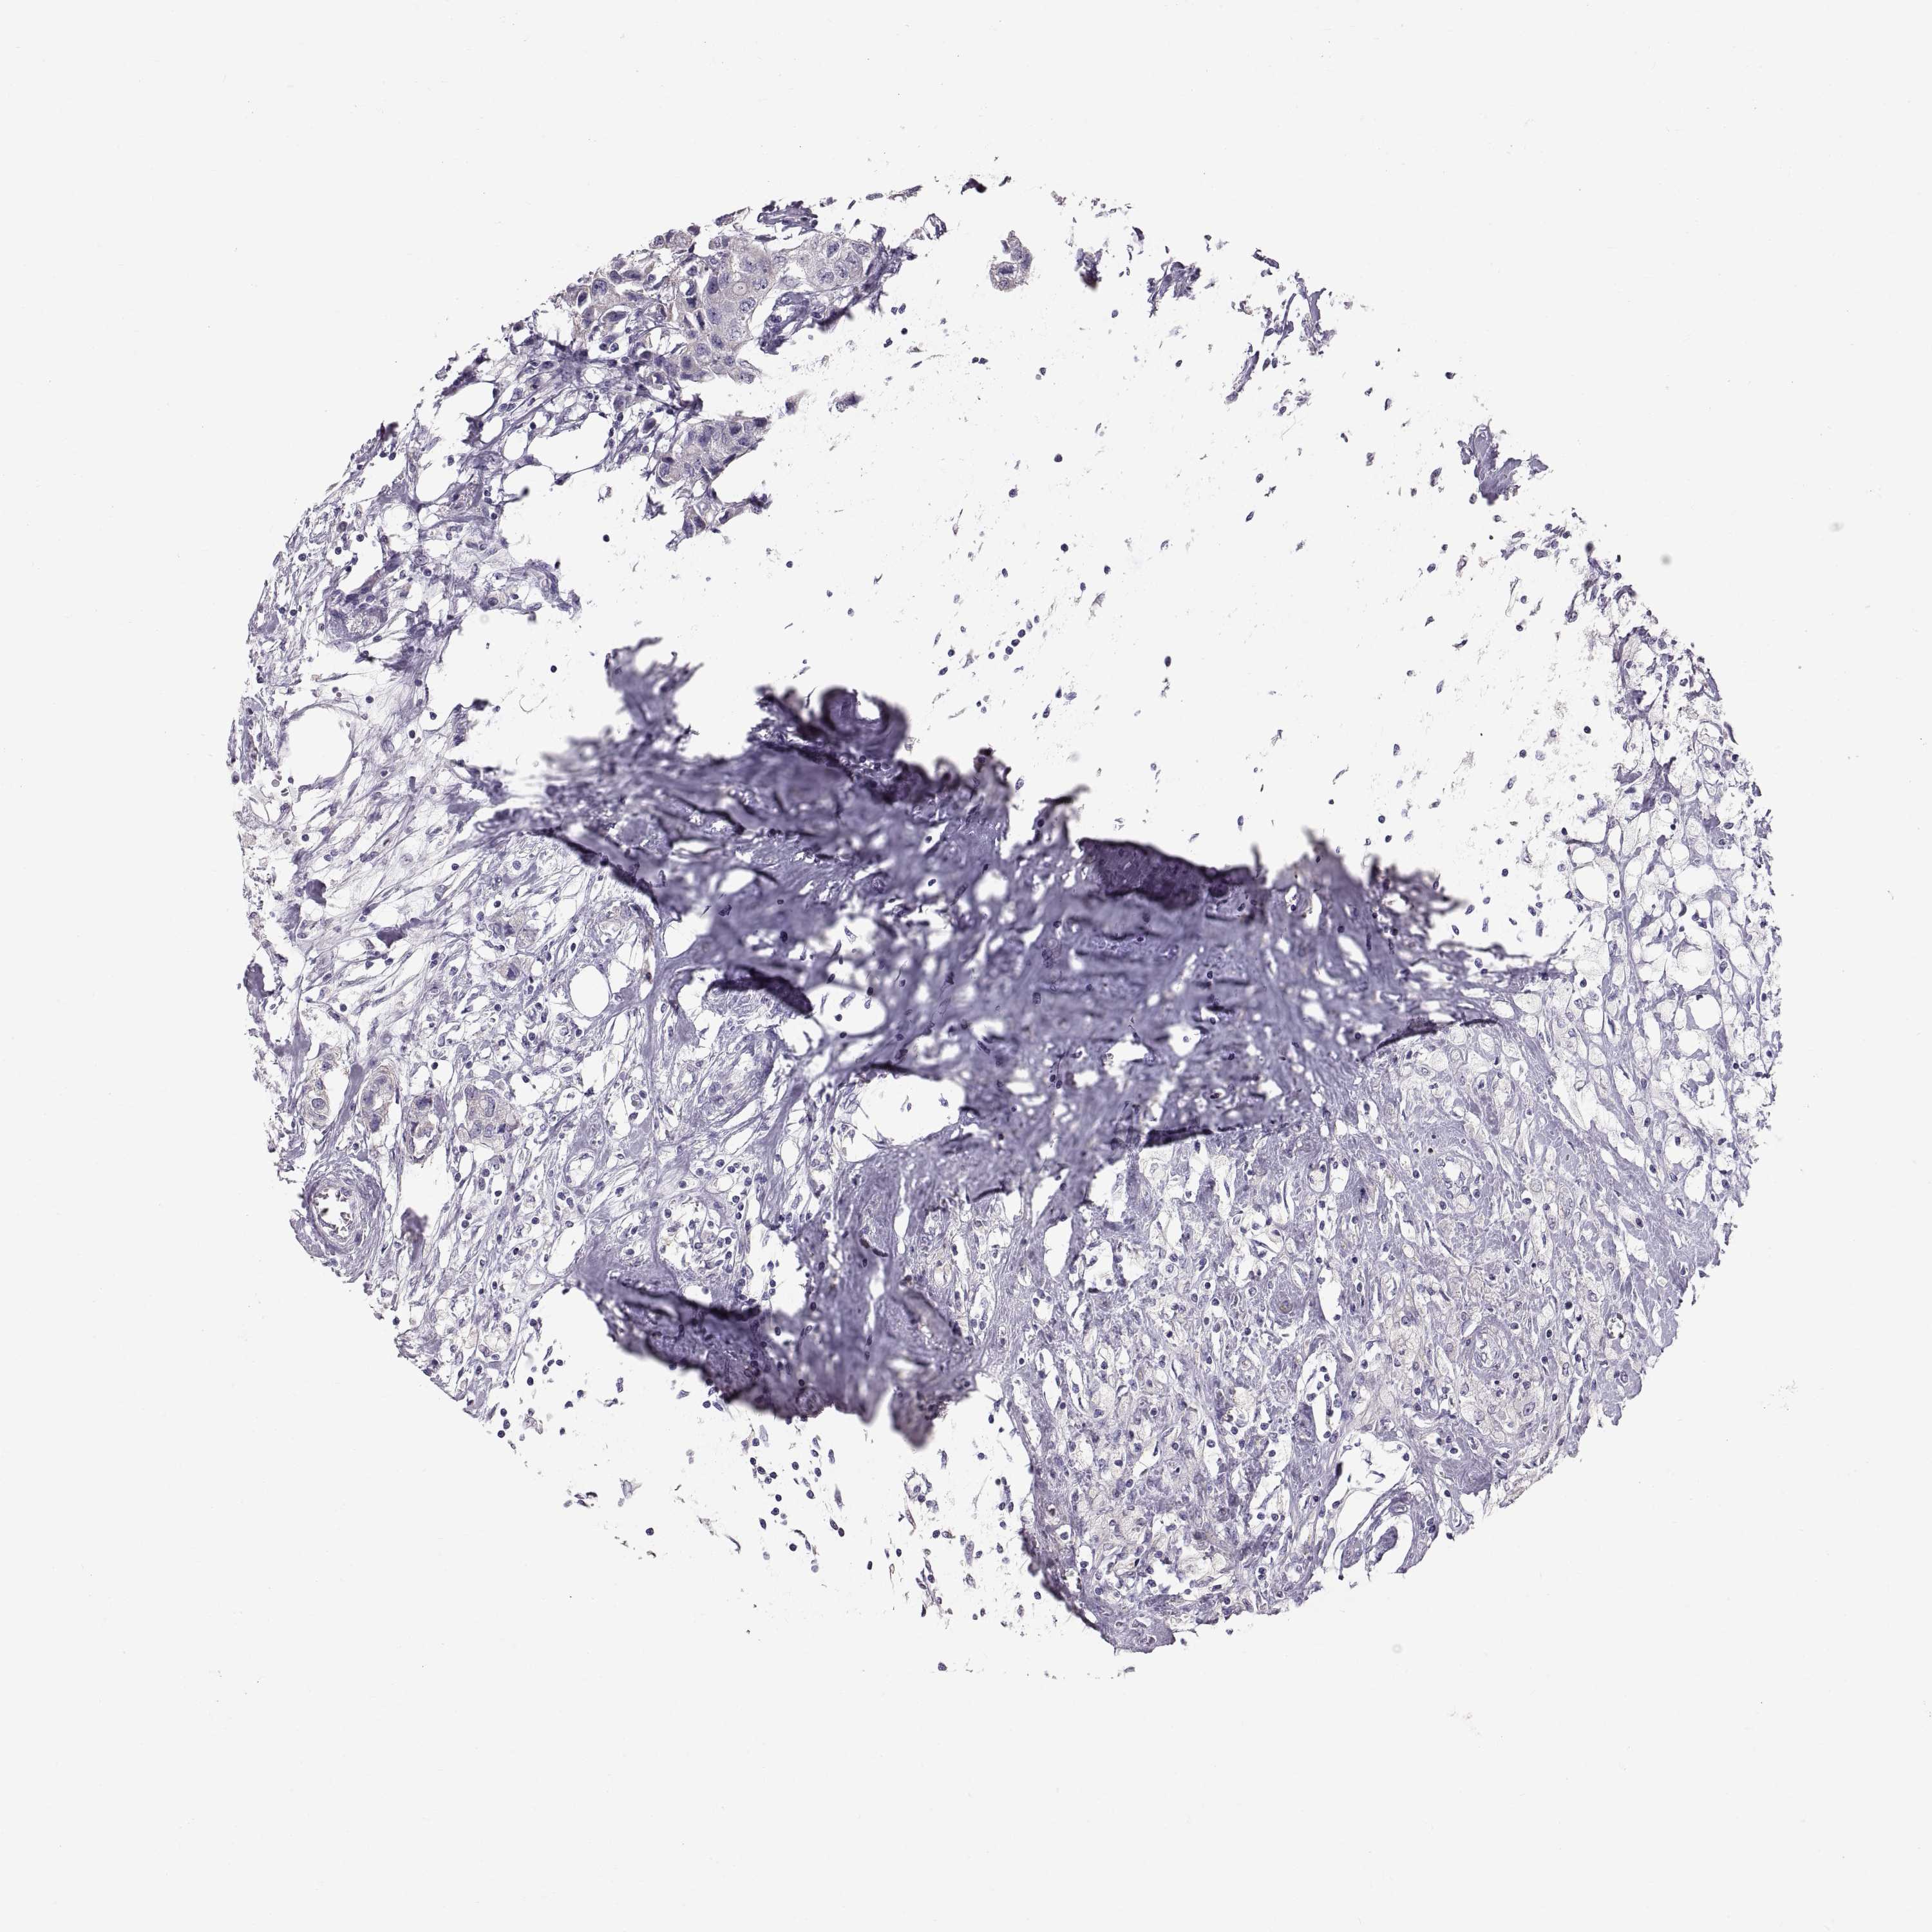

CANCER BREAST CANCER Show tissue menu

BRCA TCGA BRCA VALIDATION PROTEIN EXPRESSION

Breast cancer

Human cancer